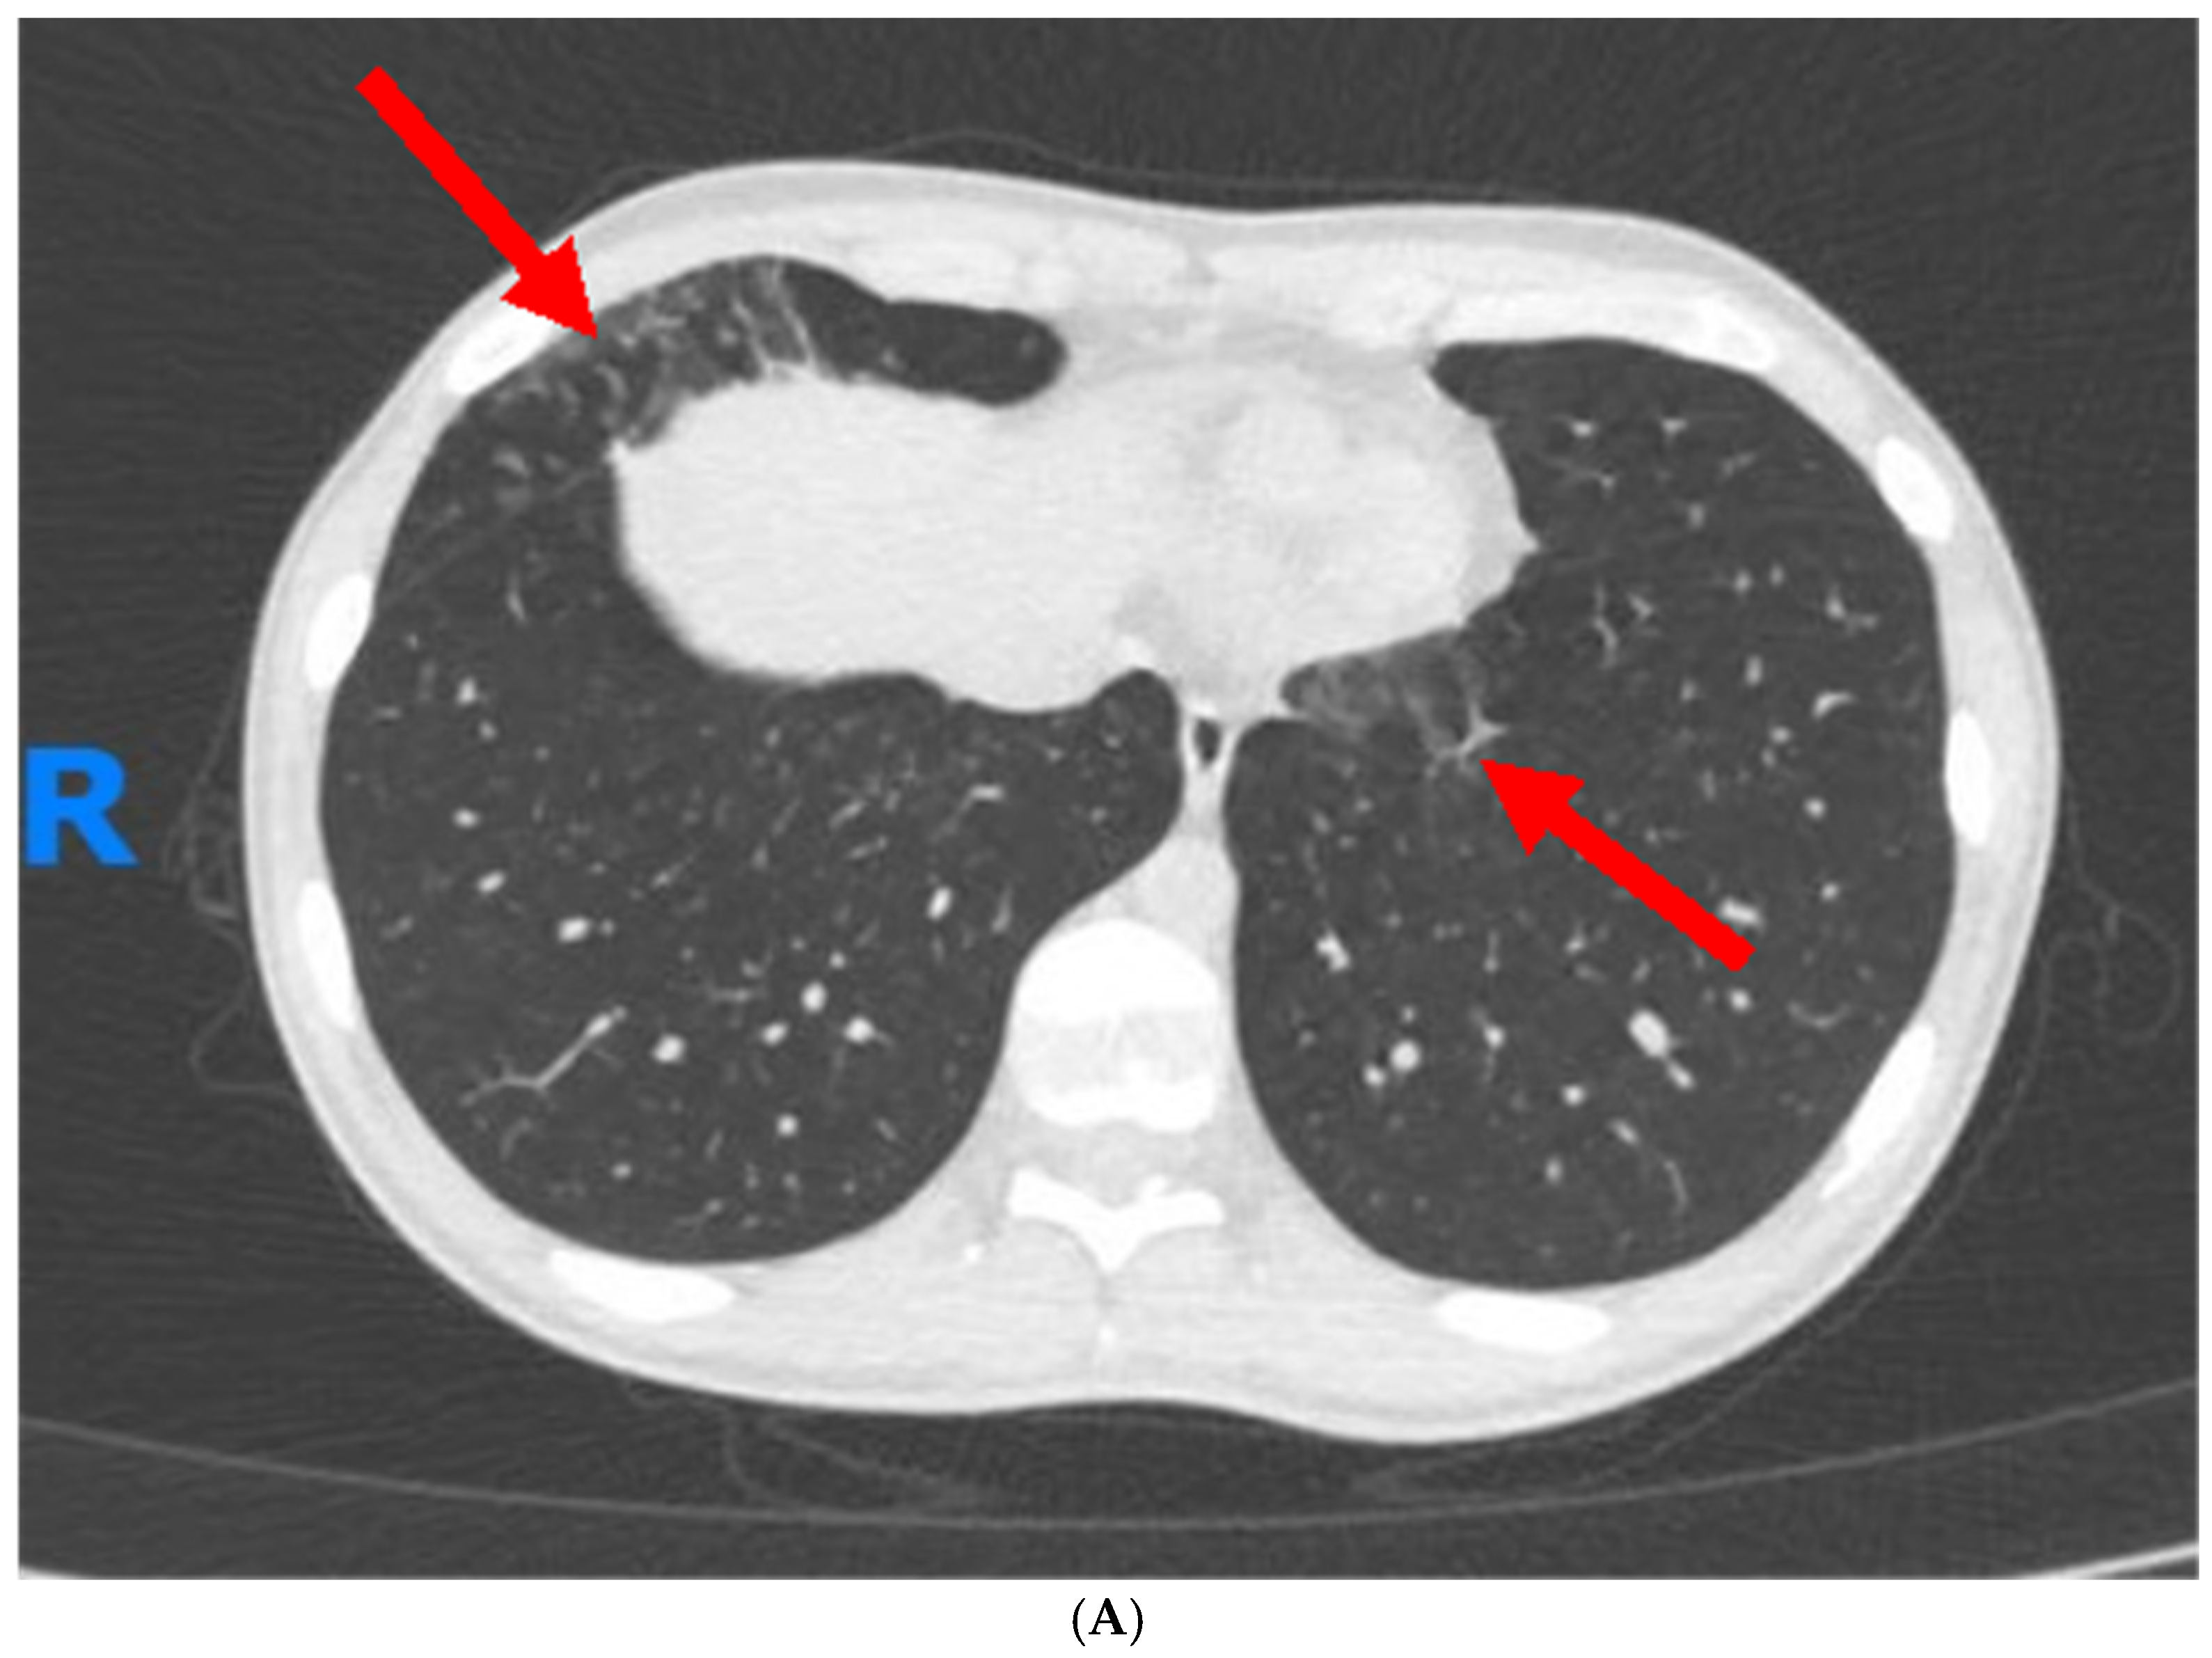

1. Case Report

- Suzuki, A.; Noro, R.; Omori, J.; Terasaki, Y.; Tanaka, T.; Fujita, K.; Takano, N.; Sakurai, Y.; Suga, M.; Hayashi, A.; et al. Pulmonary manifestation of inflammatory bowel disease: Two case reports. Respir. Med. Case Rep. 2023, 45, 101914. [Google Scholar] [CrossRef]